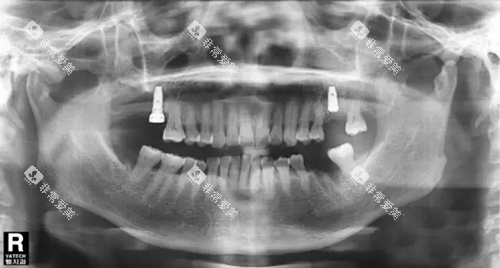

术例参考:

55岁的李先生在杭州某私立诊所做了全口登腾种植,总价6.2万元(含全瓷冠),术后改善良好,咀嚼力接近真牙。

30岁的王女士因车祸缺失半口牙,选择上海医院登腾All-on-4种植,费用4.8万元(含骨增量手术),术后3天即可正常进食。